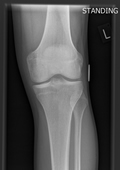

Bilateral Knee, X-ray of knees, showing osteoarthritis of the inner half of both knees (medial compartment).